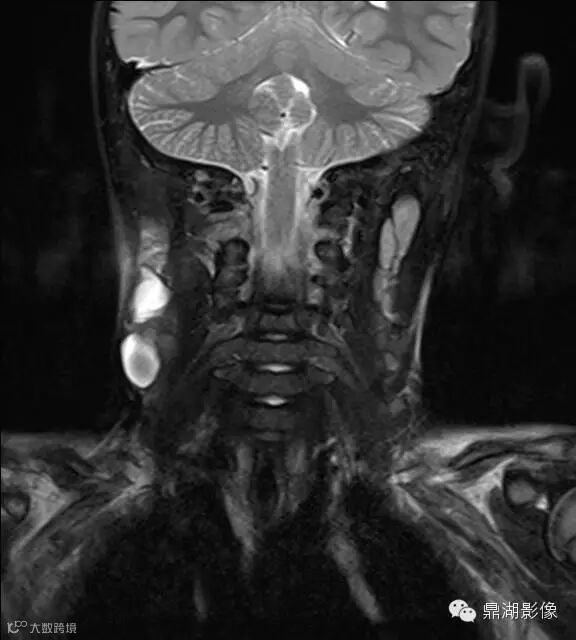

病史:男,5岁,发烧起病 39.5,咽痛,扁桃体II度,家属发现颈部肿块,质地硬,压痛。

上海儿童医院韩燕乔教授诊断:考虑淋巴结炎 ,可见杯状分层,液液平

出院临床诊断:上呼吸道支原体感染,淋巴结炎

颌面部淋巴结炎是临床较常见的一种疾病,尤其是小孩发病率更高。经常发生在颌下及颏下,有时也发生在耳后,面部和颈侧。颌面部的淋巴结炎大多是以下原因引起感染。上呼吸道感染,如扁桃体炎、咽炎、鼻炎、鼻窦炎等;口腔感染,如牙龈炎、牙周炎、口腔溃疡、冠周炎等;皮肤损伤与感染,如头面部皮肤化脓性伤口、湿疹感染、疖肿等。以上各种感染的细菌均可以随着淋巴液的循环,流经颌面部的相应淋巴结,使相应部位的淋巴结遭受细菌的侵犯,引起淋巴结的炎症。